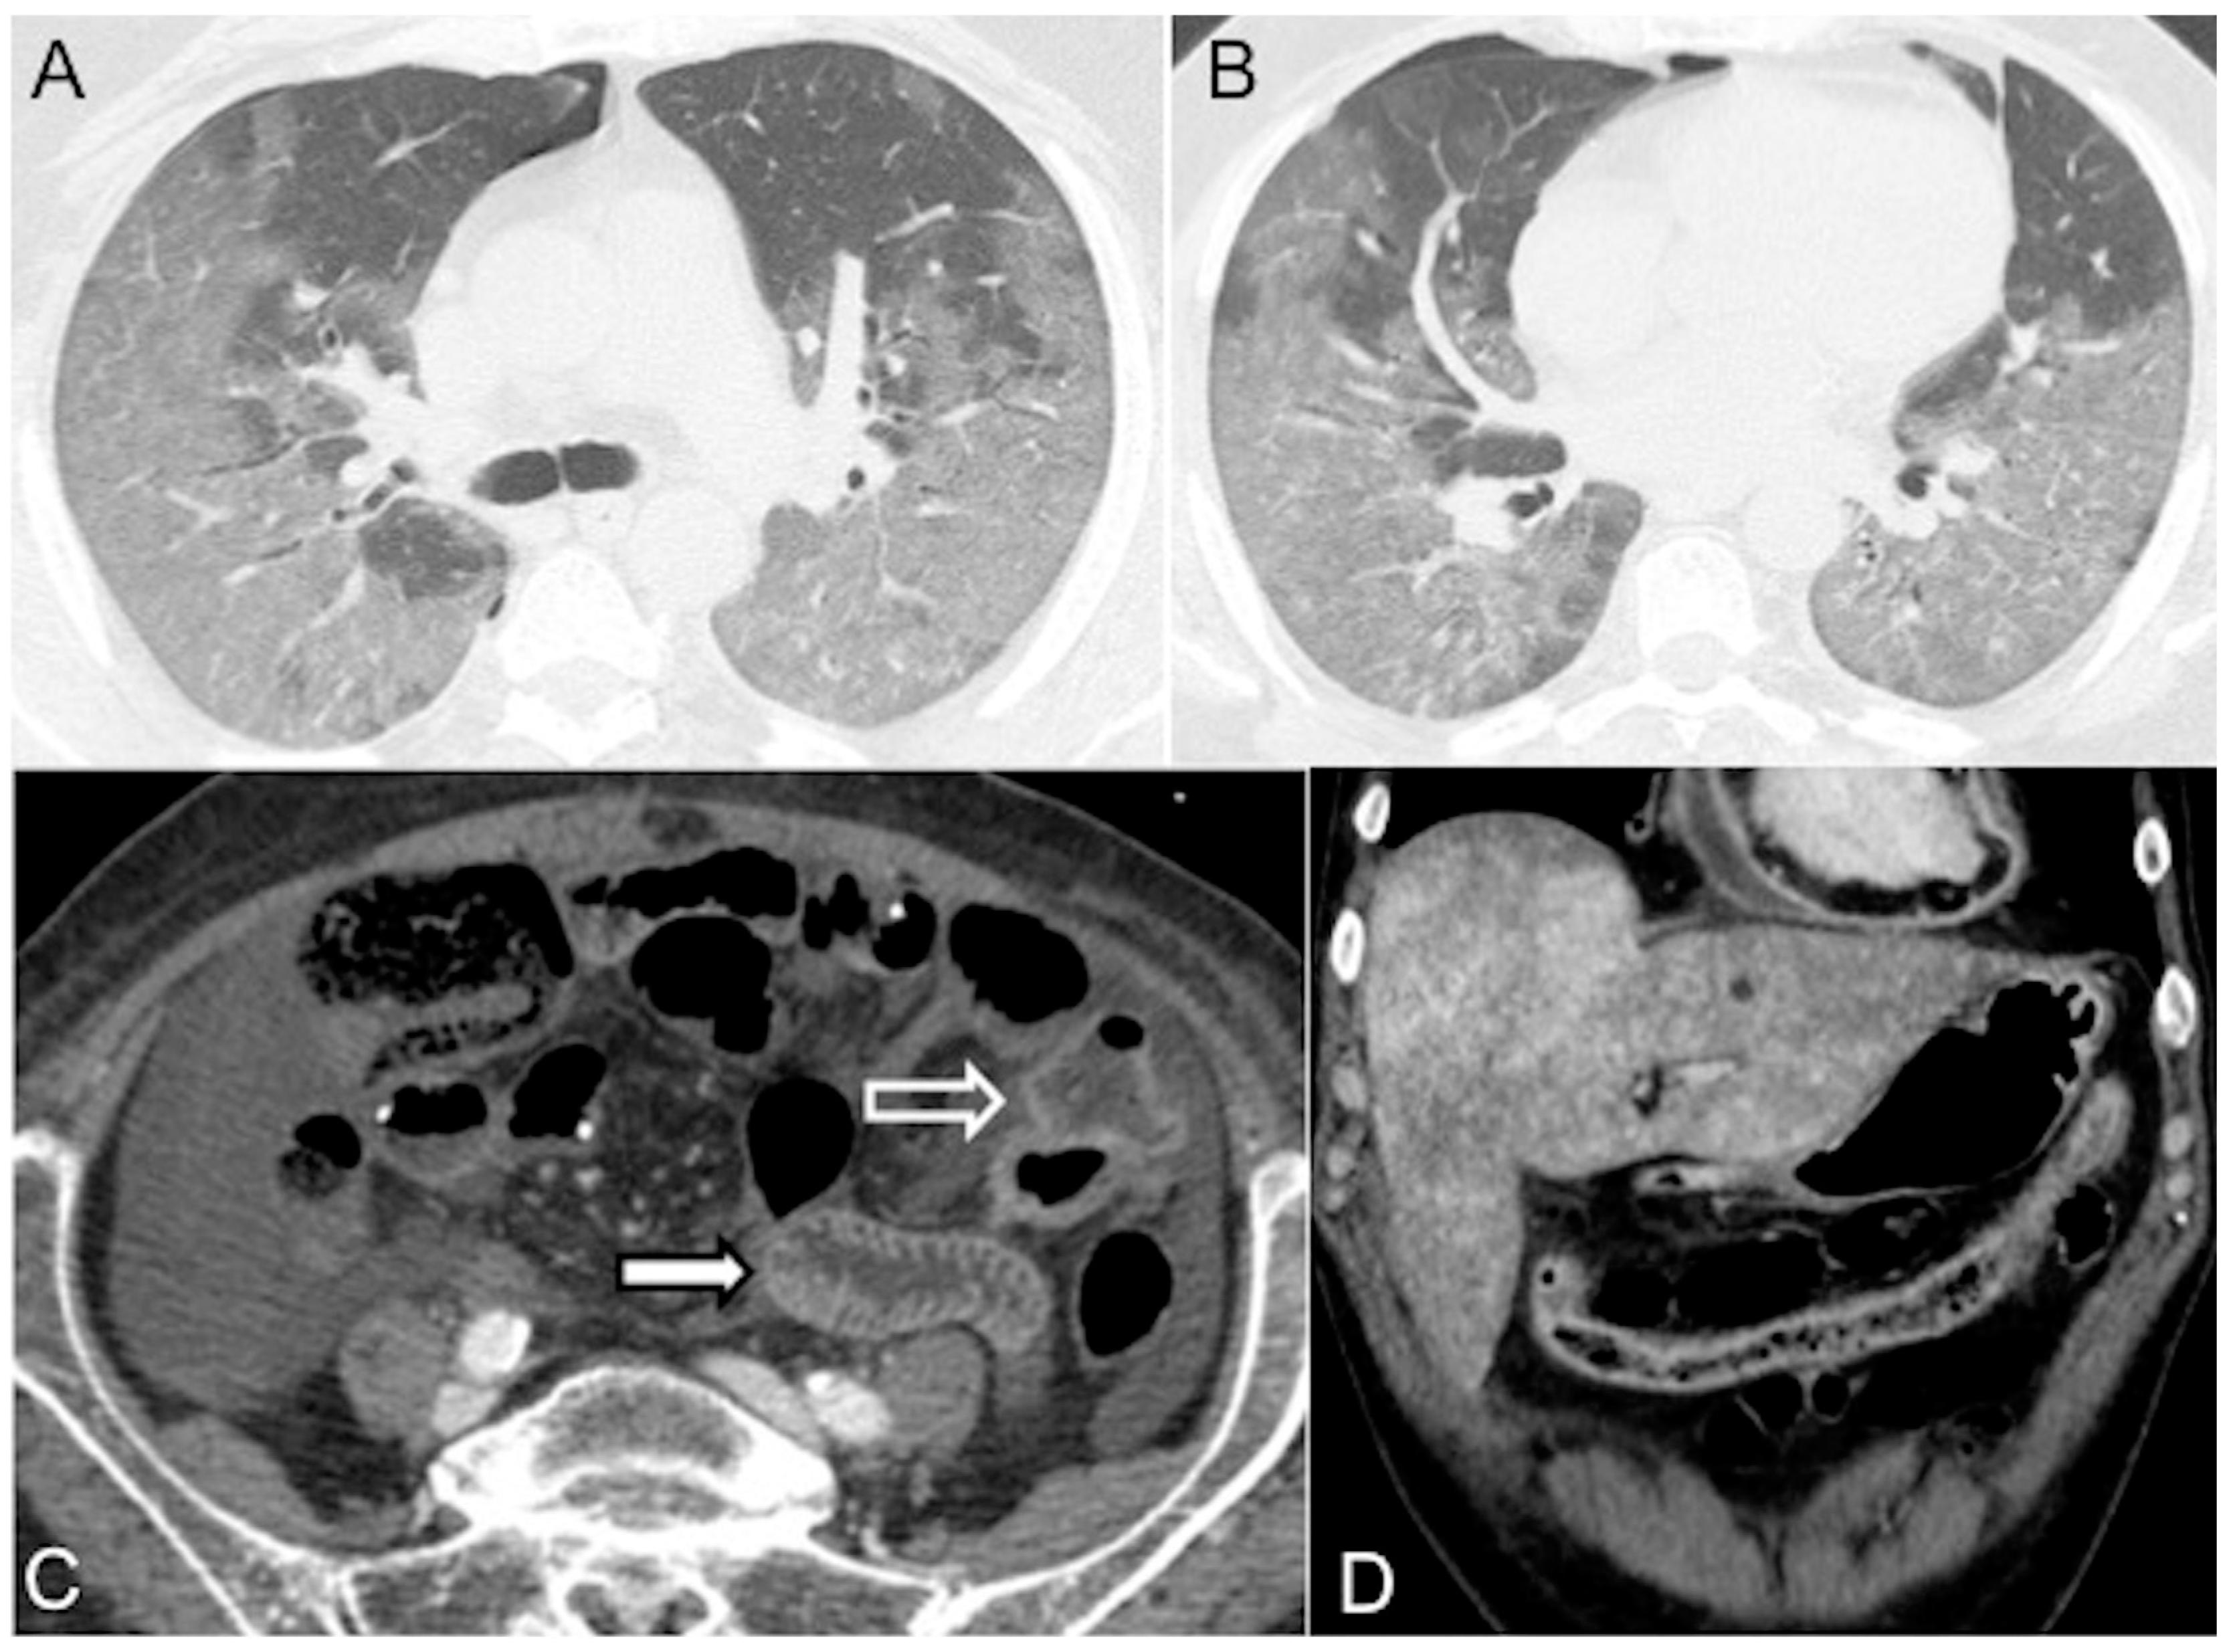

Alteration of the blood circulation dynamics may cause IV contrast to gravitate to the dependent lung segments, resulting in extremely high attenuation of the lungs posteriorly. Bilateral diffuse and lobular Ground Glass Opacification/consolidation, mainly in the middle and lower lung zones with or without an air bronchogram, may be seen [80]. Bilateral pleural effusions and lower lobar passive atelectasis are often ancillary signs of acute right-side heart failure. Acute pulmonary dysfunction and new bilateral infiltrates on chest imaging are common in septic shock from diffuse alveolar epithelial injury, leading to capillary leaks and acute respiratory distress syndrome (Figure 6A,B).

Figure 6.

Distributive septic shock in a 61-year-old male admitted to the emergency department with high fever (39 °C) and sepsis (score for sepsis, qSOFA 3) due to COVID-19 pneumonia (respiratory rate 27/min, systolic blood pressure 75 mmHg, altered mental status). (A,B) Unenhanced chest CT axial images (lung window) show bilateral parenchymal ground-glass opacities due to a diffuse alveolar damage (DAD) pattern; note mild right pneumothorax. (C) CECT axial image in the portal venous phase shows mural thickening (white empty arrow) and mucosal hyperenhancement of the small bowel (white arrow). (D) CECT coronal reconstruction in the portal venous phase shows abnormal wall thickening/enhancement in the partially collapsed transverse colon. Note associated heterogeneous liver enhancement and enhanced thickened pericardium with pericardial effusion (pericarditis).

4.2.3. Bowel (Marked Submucosal Edema and Intense Mucosal Enhancement)

Hypovolemia triggers the sympathetic system, leading to splanchnic vasoconstriction and reduced blood perfusion to the bowel. However, mucosal perfusion is preserved through autoregulation mechanisms that prevent ulceration. This results in prominent mucosal enhancement, which appears greater than the psoas muscle on non-contrast images, and submucosal enhancing edematous wall thickening (bowel wall > 3 mm) [21,27]. Severe hypotension can lead to inadequate oxygen delivery to the organs [22,28]. Reduced perfusion can cause injury to the intramural vessels, resulting in increased capillary permeability and interstitial fluid leakage into the bowel wall and lumen. This leads to decreased fluid reabsorption and eventually ileus, characterized by dilated fluid-filled loops (Figure 6C,D) [19,21,81,82,83,84]. Diffuse bowel ischemia due to vascular occlusion or non-occlusive mesenteric ischemia (NOMI) presents a challenging differential diagnosis. Both conditions can cause bowel wall thickening and luminal distention. However, arterial occlusion-related bowel ischemia does not exhibit diffuse mucosal enhancement or substantial submucosal edema. On the other hand, mesenteric venous occlusion or reperfusion in NOMI may exhibit both of these CT signs [82,83,84].